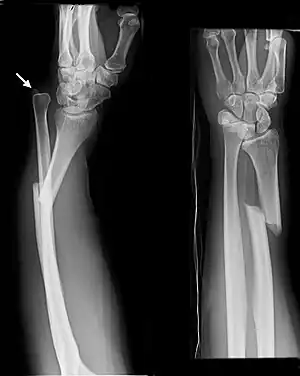

| Isolated fracture of the ulna (known as a nightstick fracture) | |

- Nightstick fracture is a fracture of the middle portion of the ulna without other fractures, and with both wrist and elbow joints preserved.[7]

Undisplaced isolated ulna fracture